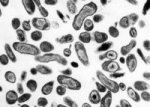

ЛишайОтрубевидный лишай. При этом заболевании грибком поражается роговой слой эпидермиса и устья фолликулов.... ЛишайОтрубевидный лишай. При этом заболевании грибком поражается роговой слой эпидермиса и устья фолликулов....